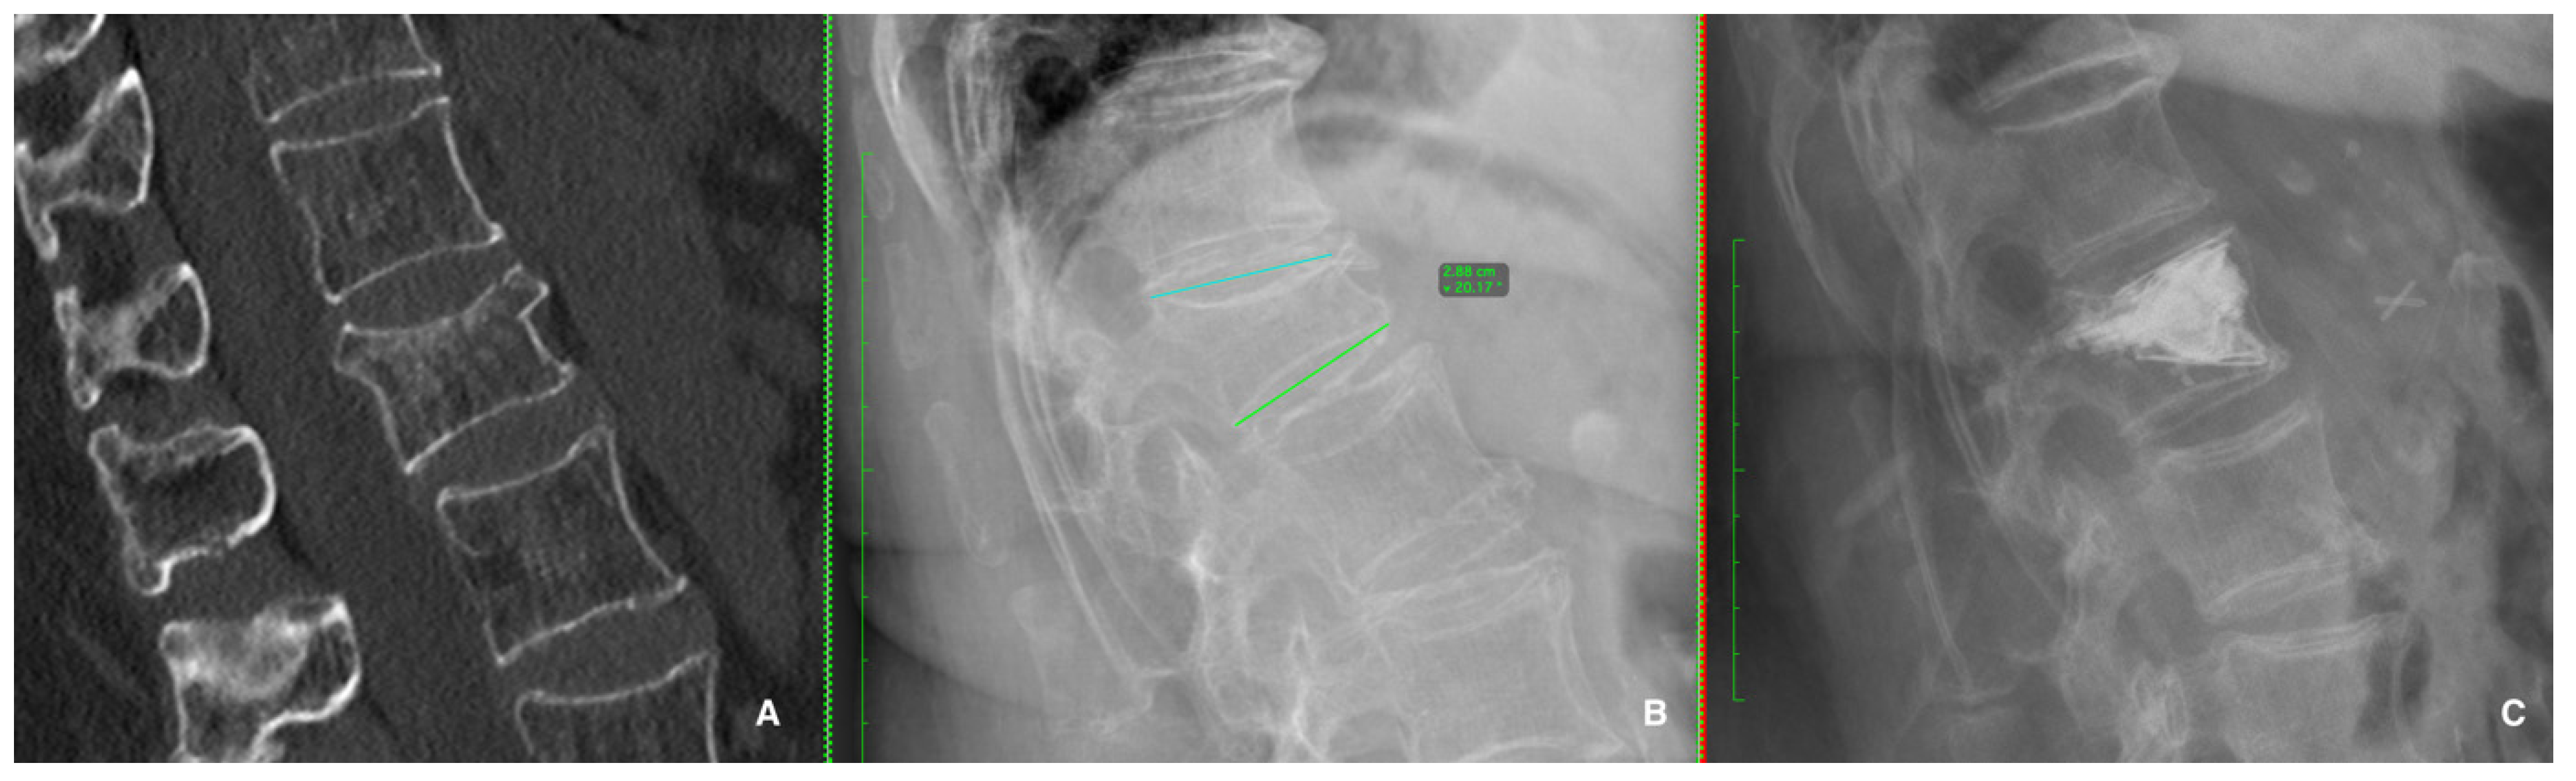

- Genant, H.K.; Wu, C.Y.; Van Kuijk, C.; Nevitt, M.C. Vertebral fracture assessment using a semiquantitative technique. J. Bone Min. Res. 1993, 8, 1137–1148. [Google Scholar] [CrossRef]